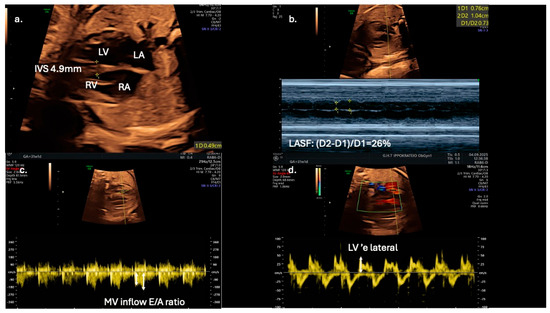

Cardiac Aftermath of Gestational Diabetes—From Intrauterine Impact to Lifelong Complications: A Systematic Review

Sophia Tsokkou, Ioannis Konstantinidis, Antonios Keramas, Vasileios Anastasiou, Alkis Matsas, Maria Florou, Alexandra Arvanitaki, Emmanouela Peteinidou, Theodoros Karamitsos, George Giannakoulas, Themistoklis Dagklis, Theodora Papamitsou, Antonios Ziakas and Vasileios Kamperidis

J. Dev. Biol. 2025, 13(4), 44; https://doi.org/10.3390/jdb13040044 - 8 Dec 2025

Background. Gestational diabetes mellitus (GDM) induces maternal hyperglycemia, which may alter fetal cardiac structure and function, increasing short- and long-term cardiovascular risks. Purpose. To systematically review the evidence on the fetal cardiac structural and functional effects of GDM, to explore the

Background. Gestational diabetes mellitus (GDM) induces maternal hyperglycemia, which may alter fetal cardiac structure and function, increasing short- and long-term cardiovascular risks. Purpose. To systematically review the evidence on the fetal cardiac structural and functional effects of GDM, to explore the diagnostic role of novel imaging and biochemical biomarkers, and to summarize the long-term cardiovascular complications associated with GDM. Materials and Methods. A systematic search of PubMed, Scopus, and Cochrane Library was conducted according to the PRISMA guidelines. All studies comparing cardiac outcomes in GDM and non-GDM pregnancies were included. Data on myocardial hypertrophy, diastolic and systolic function, imaging modalities, and biomarkers were extracted and qualitatively synthesized. Results. A total of twelve eligible studies were identified. Fetal cardiac hypertrophy and diastolic and early systolic dysfunction are common among GDM pregnancies and can be detected by dual-gate Doppler and speckle-tracking echocardiography. Abnormalities are observed in indices such as the myocardial performance index, E/A, E/e′ ratios, and global longitudinal and circumferential strain in fetuses and may persist in the neonatal period. Alterations may be more pronounced for the right ventricle compared to the left. Septal hypertrophy is associated with elevated umbilical cord pro-brain natriuretic peptide. The risk of early-onset cardiovascular disease in the progeny of diabetic mothers is 29% higher, as evidenced by population-based cohort data. Conclusions. GDM is linked to fetal cardiac remodeling and an increased long-term cardiovascular risk. Early detection and customized interventions to reduce adverse outcomes may be achieved by integrating advanced echocardiographic techniques and biomarkers into prenatal surveillance.

Figure 1